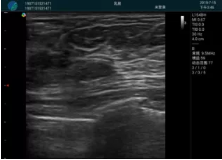

可視化甲狀腺穿刺引導(dǎo)

頸動(dòng)脈血流充盈飽滿,無(wú)外溢

肝內(nèi)血管顯示清晰,血流敏感無(wú)外溢

甲狀腺囊性結(jié)節(jié),囊壁鈣化,透聲好

甲狀腺囊性占位